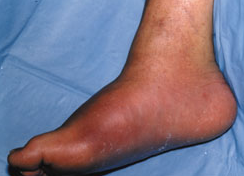

A man with type 2 diabetes mellitus sought evaluation of a hot, swollen right foot that seemed to have become “flat," consistent with Charcot joint.